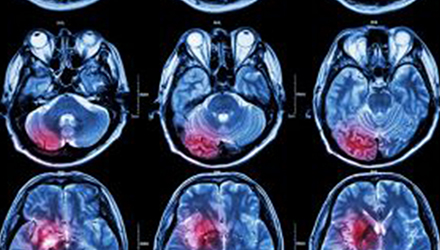

在這項研究中,研究人員使用功能核磁共振成像(fMRI)觀察大腦中血液含氧量的變化。研究人員首先研究了耳鳴患者和無耳鳴者的大腦活動,其目的是比較兩組受試者大腦處理情緒的方式。

功能磁共振成像的結果顯示,當暴露于情緒性聲音下,耳鳴患者大腦不同區域的活動比沒有耳鳴者的活動更強烈。接著,研究人員進行了更深入的研究:耳鳴患者的大腦活躍性和耳鳴嚴重程度的關系。

調查結束后,再進行功能核磁共振成像檢查。第二輪功能核磁共振成像顯示,那些耳鳴較輕的患者實際上使用了大腦不同的區域來處理情緒信息。

傳統觀點認為,大腦中的扁桃體是處理情緒的關鍵,但此次研究發現,那些不被耳鳴困擾的患者實際上使用更多大腦額葉來處理情緒。這類患者額葉活動更顯著的原因是,額葉通常更多地用于注意力、計劃和沖動的控制。